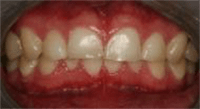

| 0 | No ETW | ![]() |

| 1 | Initial loss of surface texture | ![]() |

| 2a | Distinct defect; hard tissue loss involving <50% of the surface area | ![]() |

| 3a | Hard tissue loss involving ≥50% of the surface area | ![]() |

Dentin often involved.